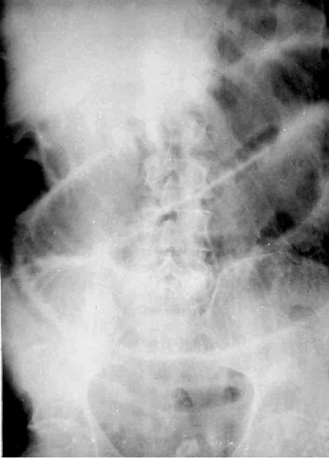

בצילום בטן סקירה ניתן לראות לולאת מעי יחידה מורחבת. אחר כך - התרחבות משנית של לולאות מעי דק וכרכשת, דופן המעי מעובה ונוזל בין לולאות המעי. עם התקדמות התהליך אפשר לראות גז בדופן המעי ובמערכת השערית (תצלום 21.4).